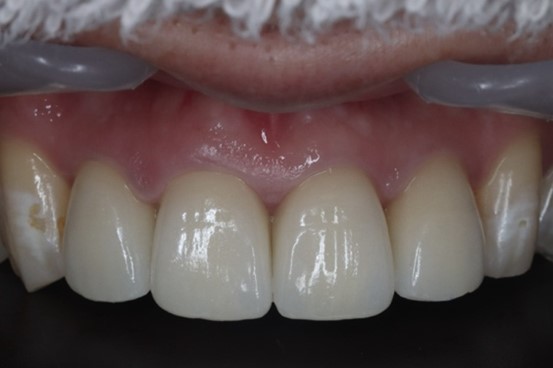

治療後の様子

歯肉の状態は非常に健康な状態に保たれ、かみ合わせも仮歯製作時と同様に良好です。

今回の患者様は歯と歯茎の境目と、前歯部の色を気にされていました。前歯の詰め物をオールセラミックの材料でやり変えることで、自然で明るい口元を実現しています。